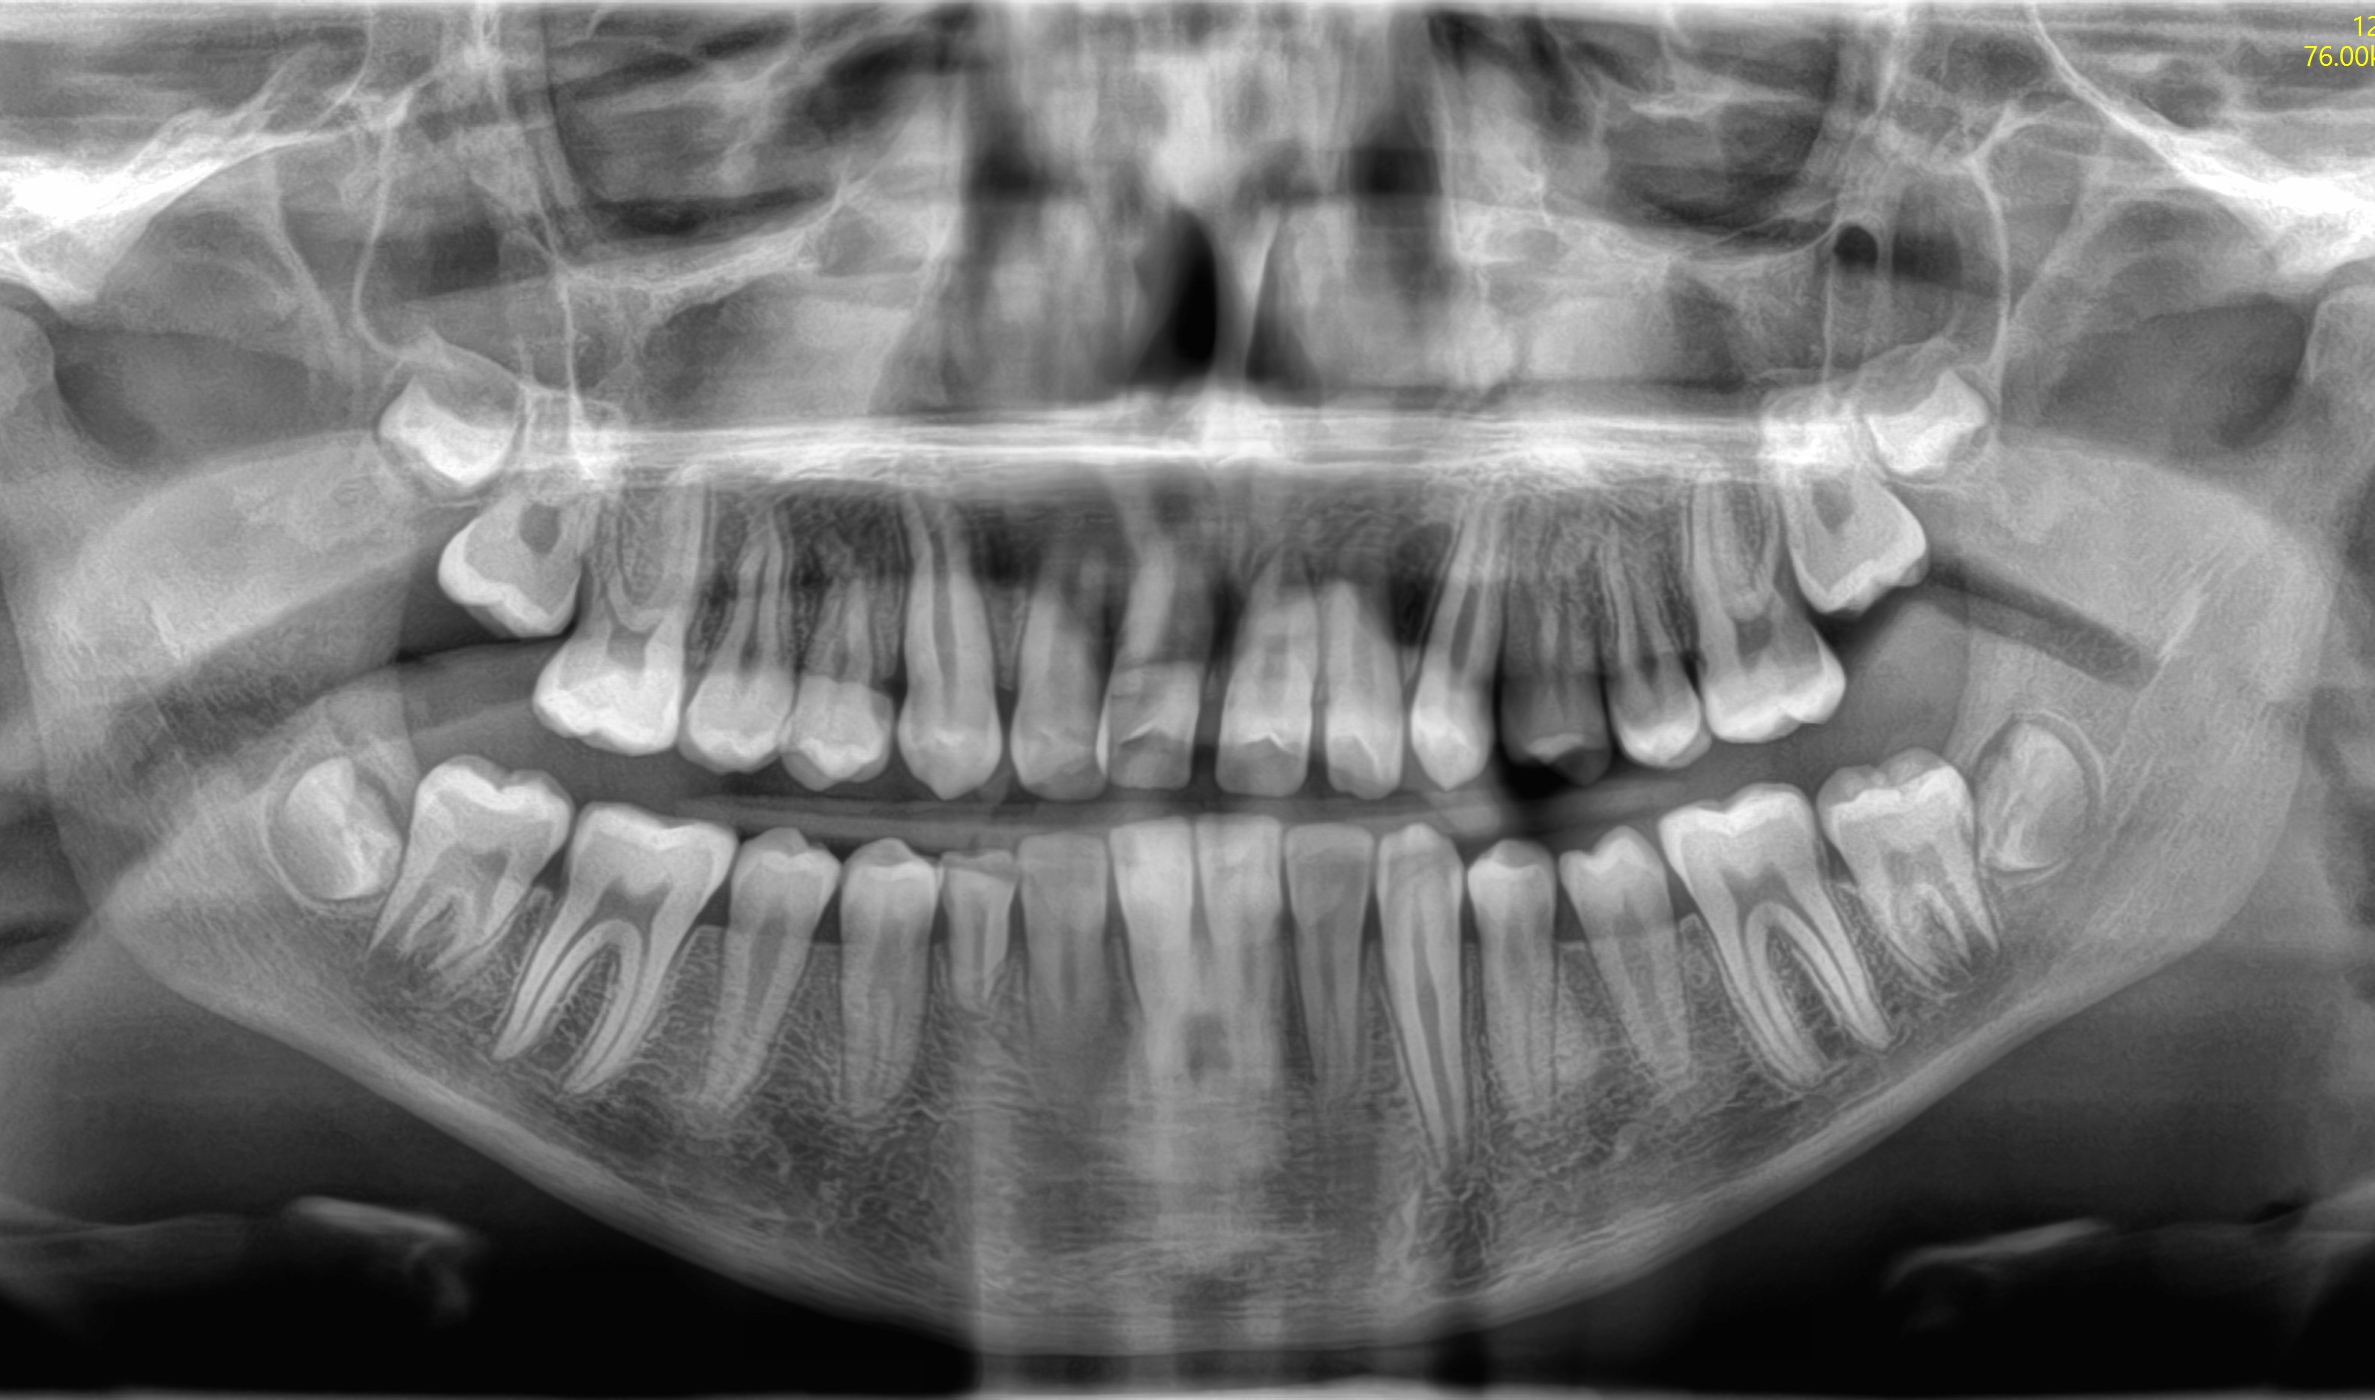

CASO 1

Estrazione di tutti e 4 i denti del giudizio per disodontiasi. Operazione chirurgica avvenuta in due sedute.